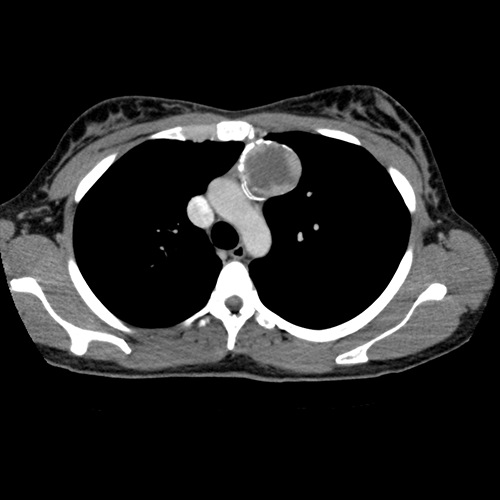

A chest CT can be used to further evaluate this soft tissue mass in the anterior mediastinum.

Pertinent Imaging Observations

Click on the links below to view images from the study, and assess these key findings as best you can.

Teratoma, thymoma, and lymphoma are three common anterior mediastinal masses. A teratoma and thymoma are most likely considering the calcifications.

A 65-year-old male was incidentally found to have a heterogeneous, peripherally calcified mediastinal mass during pre-operative workup. We will consult thoracic surgery. The patient may require mass resection considering the heterogeneous features with imaging follow-up.